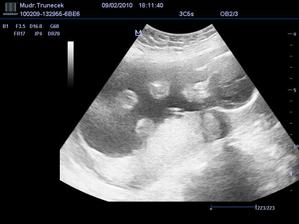

Náš František a jeho mladší sourozenec

Dne 17.10.2009 mamka zjistila, že, ač neplánovaně, budu mít sourozence.TP je zatím 21. 6.2010.